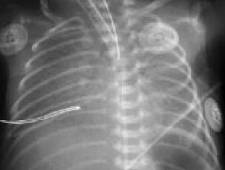

Выраженное снижение пневматизации легких, воздушные бронхограммы, границы сердца практически не различимы, стёрты (Рис.6).

Рисунок 6. РДС. Рентгенограмма грудной клетки в прямой проекции, в горизонтальном положении. Интенсивное мелкоточечное затемнение легочных полей - с-м "матового стекла", на фоне которого не дифференцируется тень средостения. Визуализируются линейные просветления, обусловленные заполненными воздухом бронхами - "воздушная бронхограмма". ( Диагностика и лечение РДС недоношенных // метод. рекомендация, 2007)